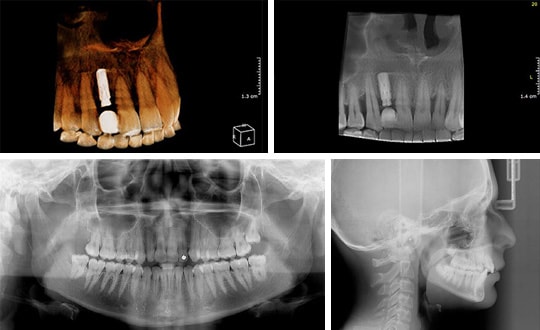

Cranex 3Dx combine performances de haut niveau, facilité d'utilisation et valeur

Cranex 3Dx possède 5 champs de vision pour une imagerie précise en 3D, de la dent prise individuellement à l'ensemble de la région maxillofaciale.

Les consultations peuvent beneficier de la performance de pointe apportée par Cranex 3Dx grâce à une excellente imagerie panoramique et céphalométrique et à une imagerie 3D avancée utile dans plusieurs domaines d'application.